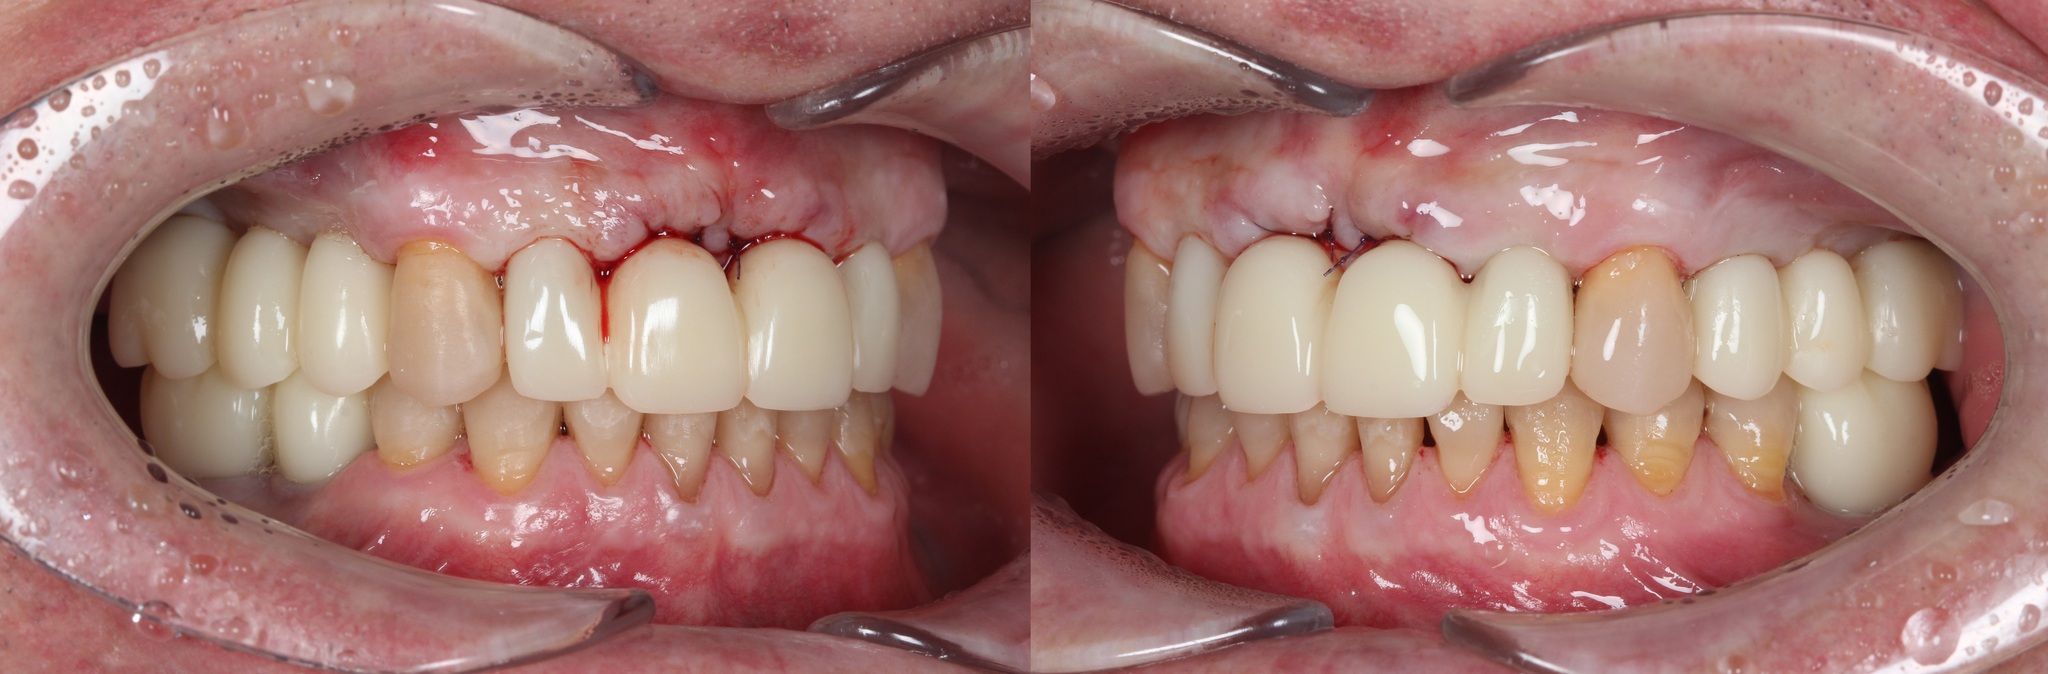

Спустя две недели произведена фиксация временных коронок.

Коронки на имплантатах на нижней челюсти:

Параллельно я удалил два центральных верхних резца, после чего были зафиксированы все остальные временные коронки.

Подчеркну - коронки временные (!), все они будут заменены на постоянные.

А как стало на промежуточном этапе:

Согласитесь, выглядит очень даже неплохо, если опустить цвет.